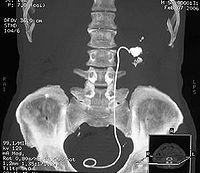

90%以上的输尿管结石在尿路平片上可被显示,草酸钙显示最佳,但需与腹腔淋巴结钙化盆腔静脉石阑尾粪石和骨岛角相鉴别。静脉尿路造影主要了解结石的部位和肾功能与有无积水,必要时行大剂量尿路造影及放射性核素肾图检查,均能进一步了解肾功能情况。膀胱镜检查与输尿管插管在结石处受阻,并拍平片钙化阴影在导管的同一平面,即能肯定输尿管结石的诊断。阴性结石用空气为对比剂作逆行造影摄片,则可显示结石的存在。另外CT及B型超声检查有助于对X线平片不显影结石的诊断。

肾与输尿管结石